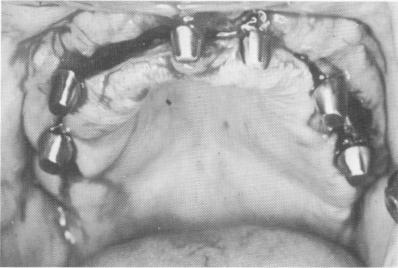

A specially prepared tray was made and an elastic impression taken of the ridge area with the continuous groove (Fig. 11-169). The master stone mode] was poured into the impression. The shallow groove in the separated hardened stone model was deepened to the various depths indicated by Panorex studies of the entire jaw (Fig. 11-170). A cobalt-chrome casting was made. Like individual blades, it was wedge-shaped.

During the following visit, the tissue was once again incised and reflected, and the continuous blade

was placed inside the original groove (Fig. 11-171). It was then tapped deeper with a plastic-headed mallet and inserting instrument until its shoulder was buried (Fig. 11-172). The site was closed with interrupted sutures (Fig. 11-173), and a prefabricated

Fig. 11-171. A one-piece continuous blade was inserted into the groove. (From Linkow, L. I., and Weiss, J. L.: The endosseous blade: a progress report, Prom. Dent., No. 5, 1969.)

Fig. 11-172. The blade was tapped deeper until its shoulder was slightly below the alveolar crest.

3 One piece continuous blade inserted into groove in upper dental arch

4 Dental blade tapped until its shoulder is little below alveolar crest